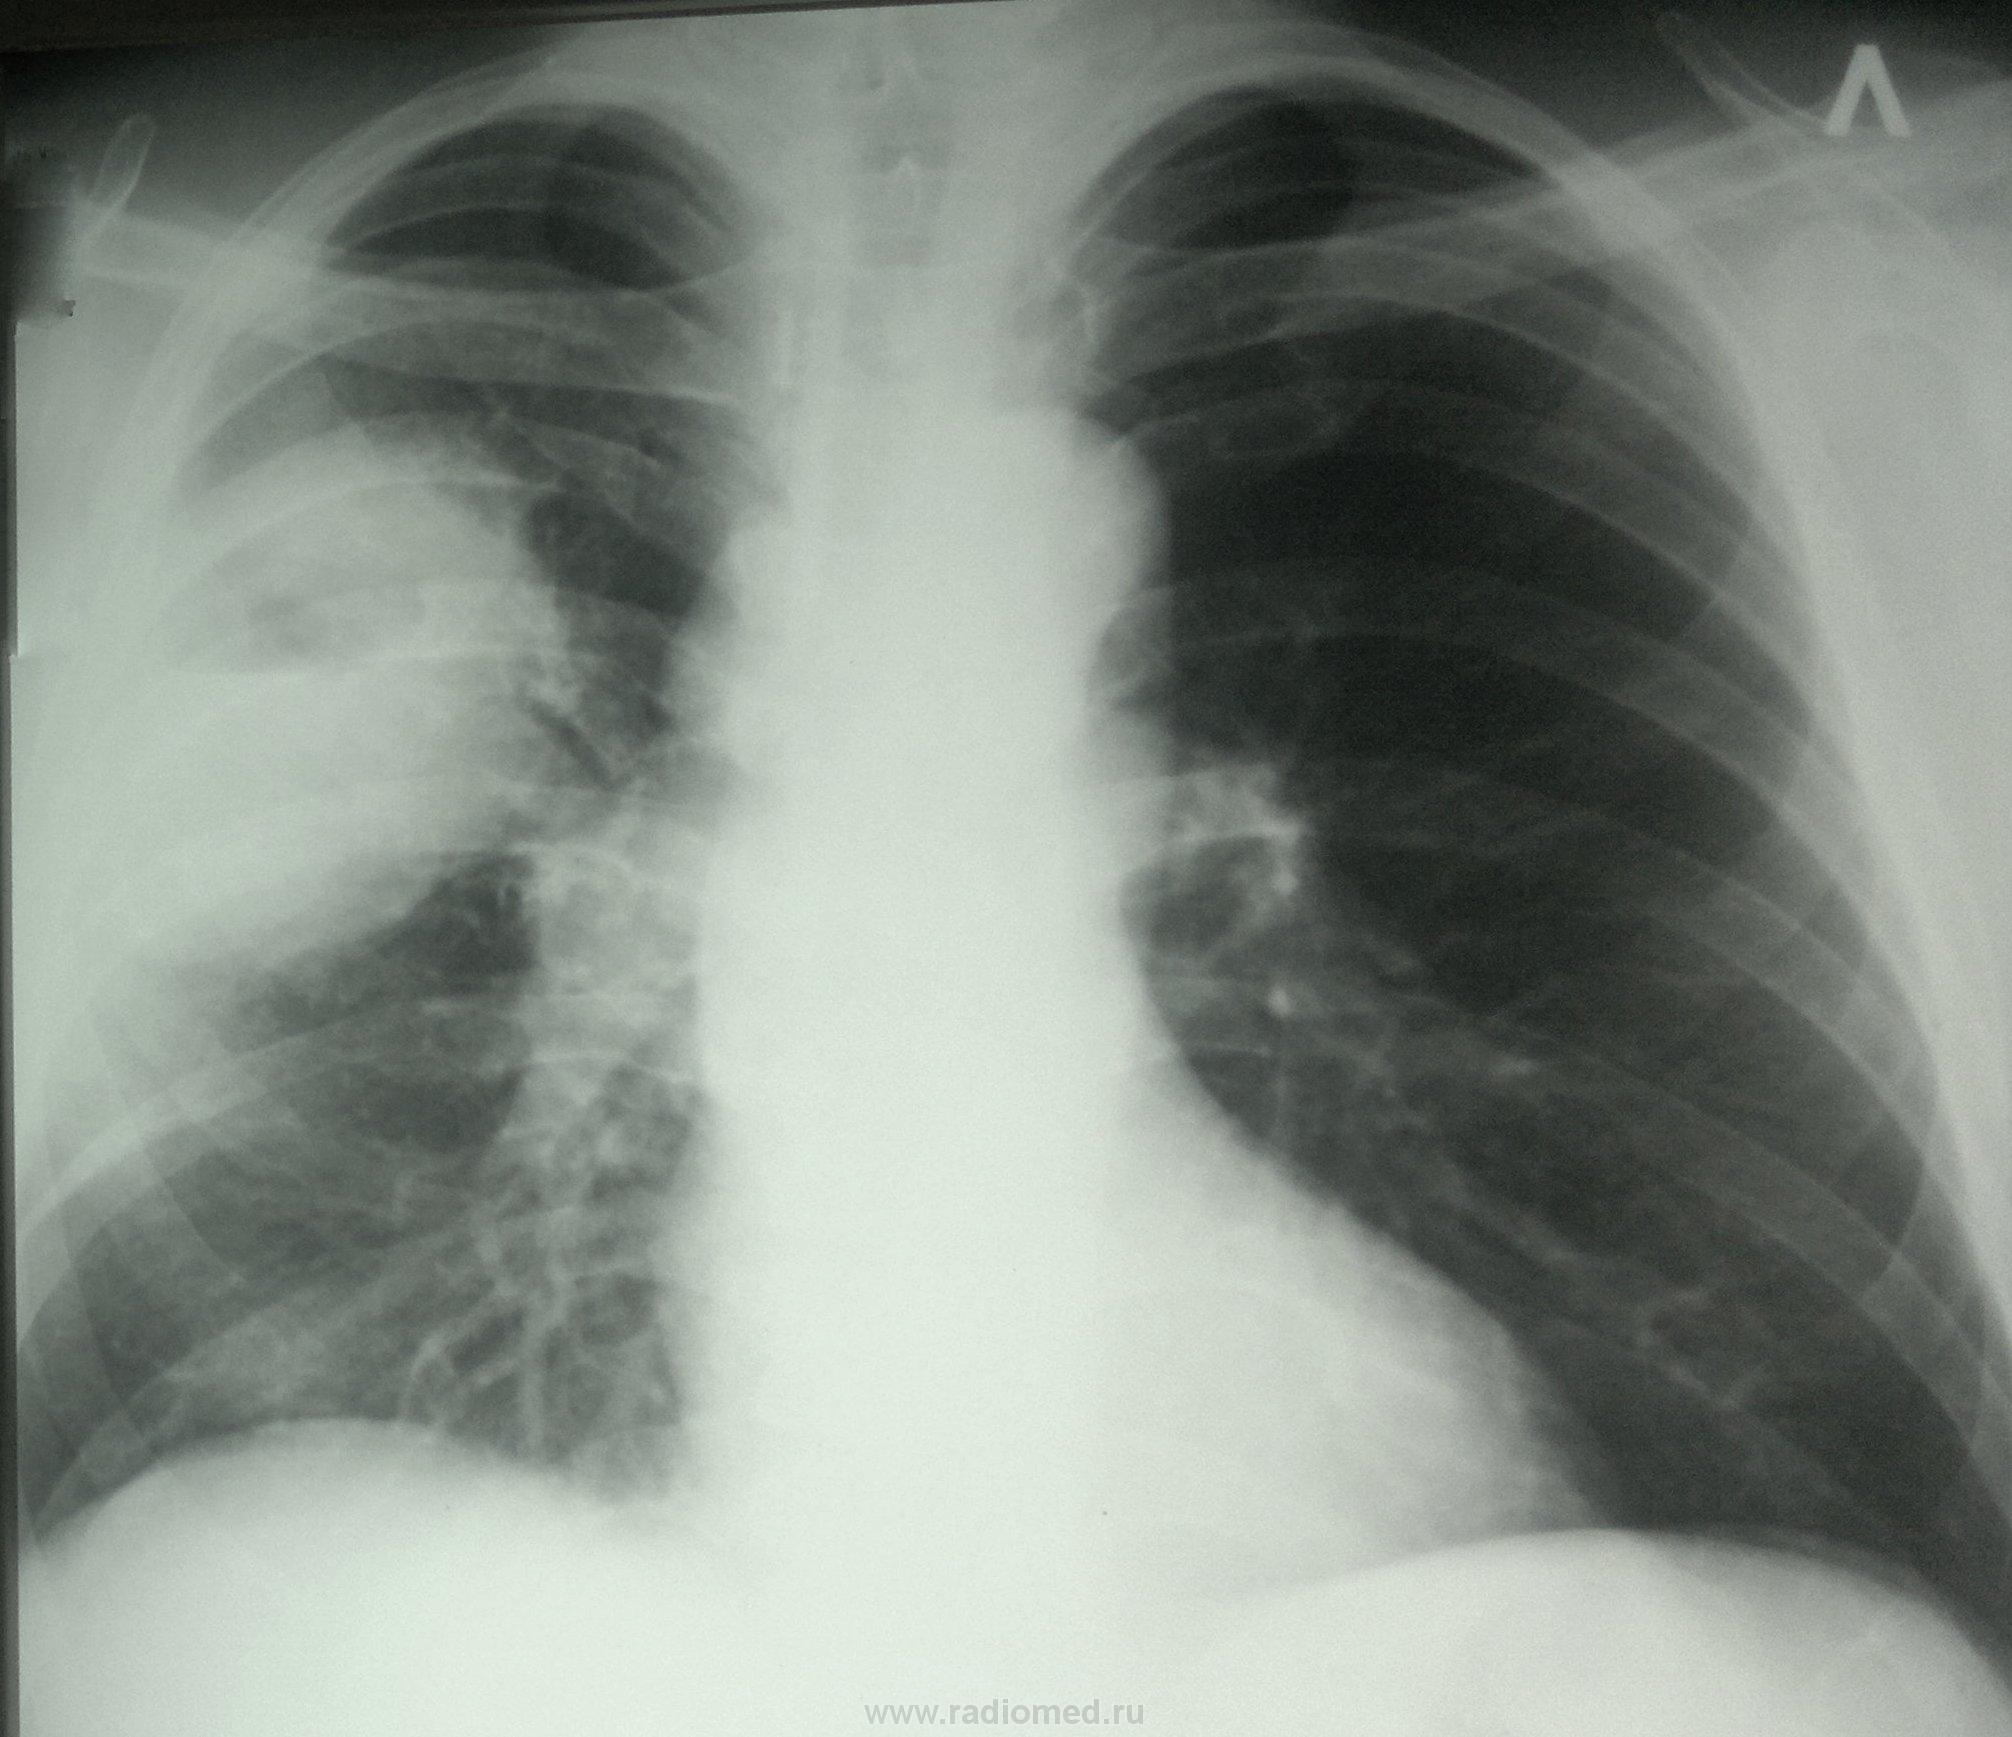

Обратился с жалобами на подкошливание, слабость. Р-гр. от 06.12.13

от стац. лечения отказался. Лечился на дому.

Выставил: Абсцедирующая пневмония в\доли правого легкого. Смущает отсутствие динамики.

имхо: скорее всего, имеем дело с абссцедирующей пневмонией, с прогрессированием инфильтрации, появлением лимфоаденопатии в правом корне.Против рака говорит отсутствие контуров затенения в верхнем отделе( это не узловое образование, а инфильтрация; нижний контур затения чёткий , за счёт того, что инфильтрат ограничен междолевой плеврой),отсутствие признаков бугристости и лучистости контуров затенения. Для уточнения показана КТ лёгких, как компромиссный вариант, линейная томография на структуру образования и корень правого лёгкого.Может быть, что-то даст если датчик аппарата УЗИ поставить в межрёберные промежутки на уровне затения справа (если есть практический опыт работы в этой области).

При абсцессе он загибаться должен и полным ртом откашливать - здесь за много дней динамики совсем нет, в правом корне что-то подозрительно круглит.. Я за версию периферического рака с распадом и мтс в лимфатические узлы корня. В любом случае, просто лечить уже хватит, нужно подключать другие методы диагностики

Еще один сильный аргумент в пользу рака - толстая стенка вокруг полости